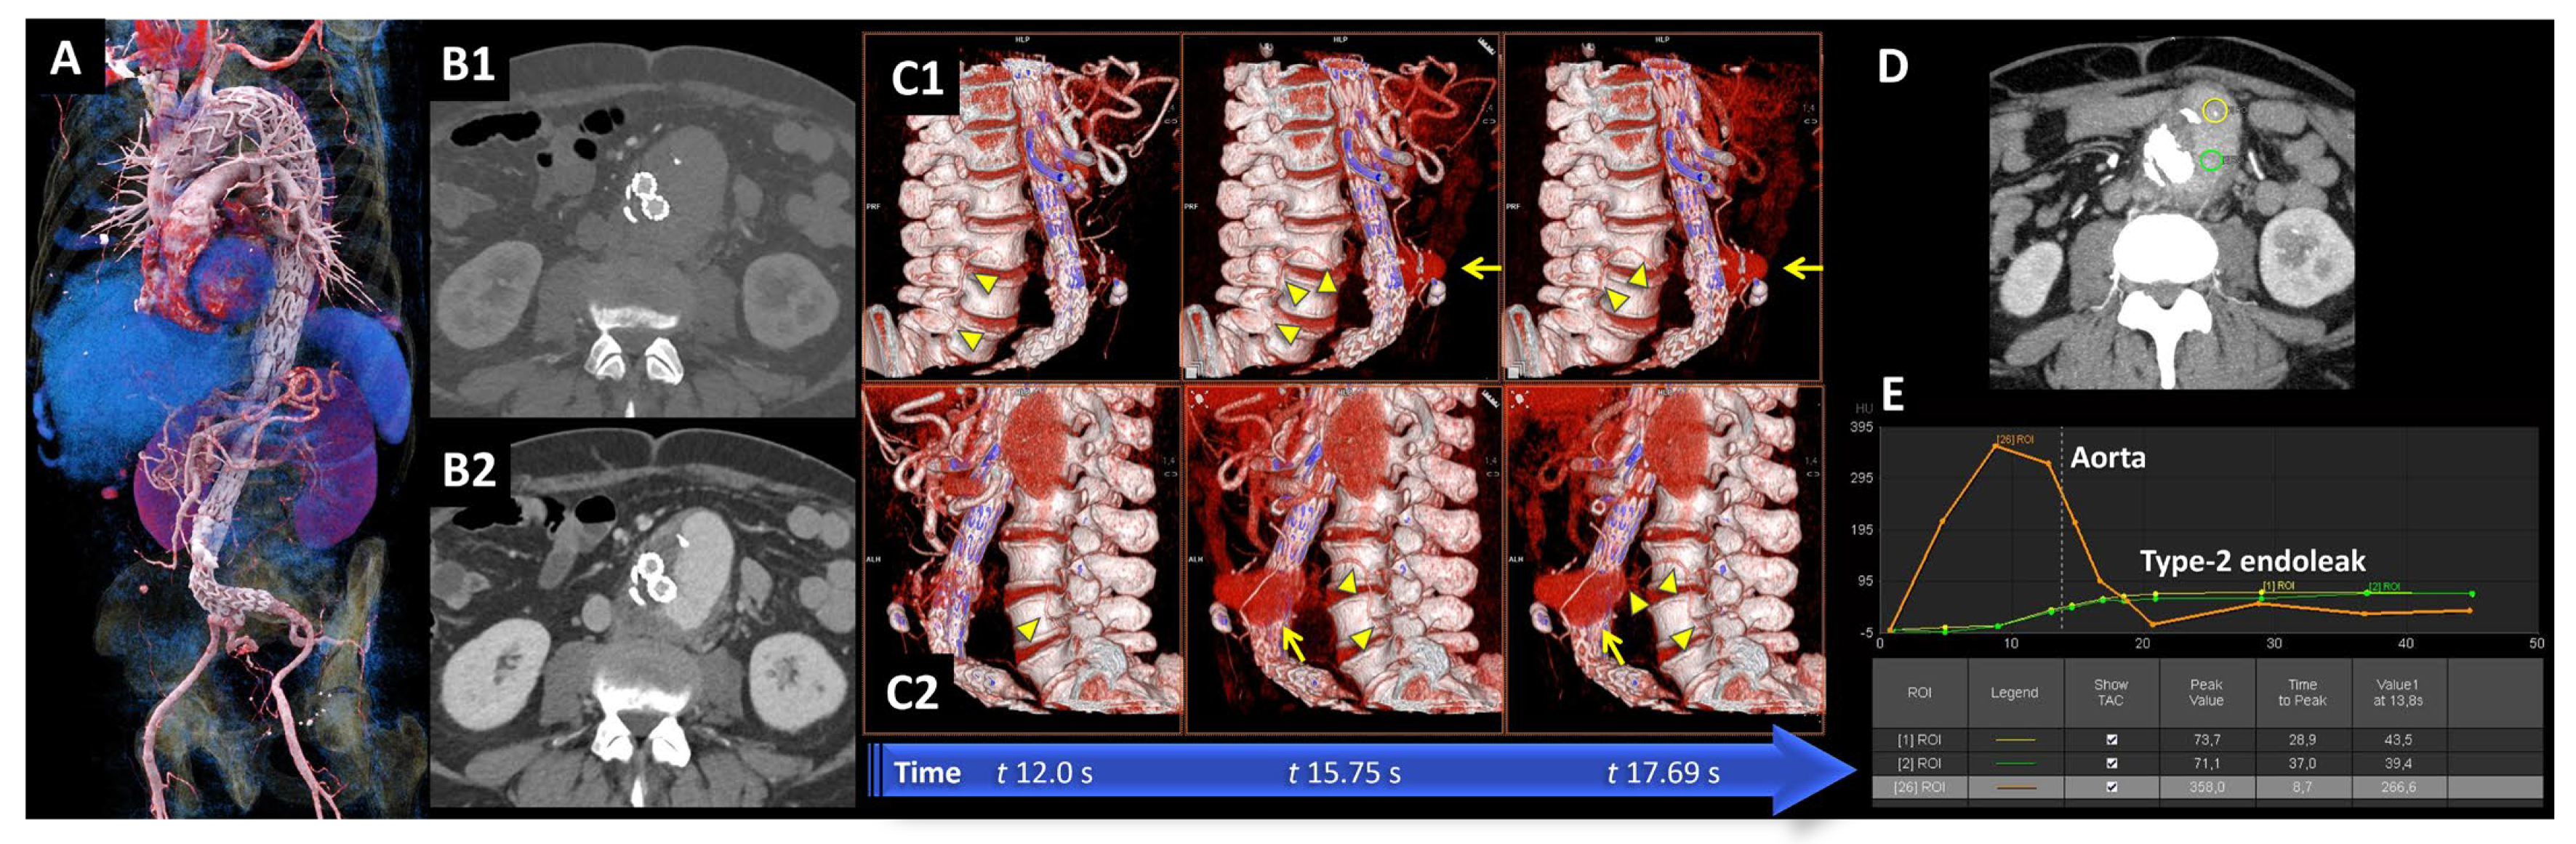

- Berczeli, M.; Chinnadurai, P.; Osztrogonácz, P.; Peden, E.K.; Bavare, C.S.; Sótonyi, P.; Chang, S.M.; Lumsden, A.B. Dynamic Computed Tomography Angiography is More Accurate in Diagnosing Endoleaks than Standard Triphasic Computed Tomography Angiography and Enables Targeted Embolization. Ann. Vasc. Surg. 2022, 88, 318–326. [Google Scholar] [CrossRef]

- Berczeli, M.; Lumsden, A.B.; Chang, S.M.; Bavare, C.S.; Chinnadurai, P. Dynamic, Time-Resolved Computed Tomography Angiography Technique to Characterize Aortic Endoleak Type, Inflow and Provide Guidance for Targeted Treatment. J. Endovasc. Ther. 2022, 29, 11–22. [Google Scholar] [CrossRef]

- Berczeli, M.; Chinnadurai, P.; Legeza, P.; Peden, E.K.; Bavare, C.S.; Chang, S.M.; Lumsden, A.B. Dynamic, Time-Resolved CT Angiography After EVAR: A Quantitative Approach to Accurately Characterize Aortic Endoleak Type and Identify Inflow Vessels. J. Endovasc. Ther. 2023, 30, 123–131. [Google Scholar] [CrossRef]